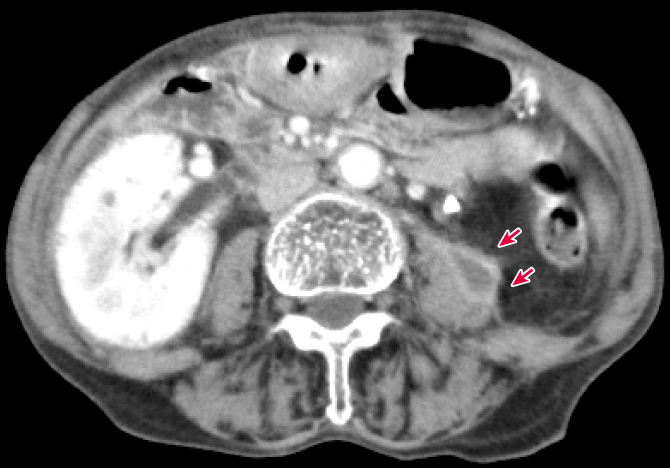

70歳代女性.糖尿病と左尿管結石による膿腎症の既往があり尿管ステントが留置されており,1週間前に泌尿器科でステント交換が行われている.昨日より38℃の発熱があり腰背部痛も出現したため総合内科外来を受診した.